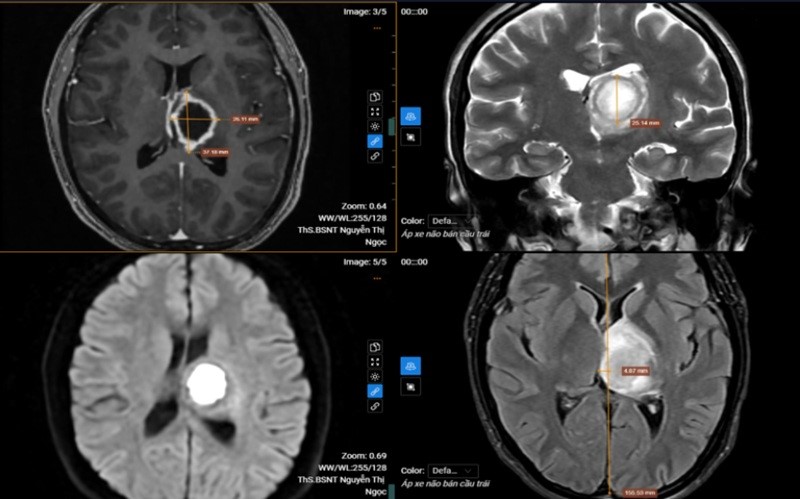

Kết quả chụp cộng hưởng từ (MRI) sọ não phát hiện tổn thương khu trú tại vùng đồi thị – vành tia bên trái, kích thước khoảng 26x37x25 mm. Tổn thương dạng dịch, ranh giới rõ nhưng bờ không đều, trung tâm có hiện tượng hạn chế khuếch tán và ngấm thuốc viền sau tiêm. Vùng não xung quanh xuất hiện phù nề, tạo hiệu ứng khối làm đẩy lệch đường giữa của não sang phải khoảng 5 mm.

Sau khi hội chẩn chuyên môn, các bác sĩ chẩn đoán bệnh nhân mắc áp xe não bán cầu trái và chỉ định nhập viện điều trị nội trú theo phác đồ chuyên khoa để tránh nguy cơ tiến triển nặng. Khi nhận kết quả bệnh nhân đã rất “sốc” vì không nghĩ mắc bệnh lý nghiêm trọng tới vậy.